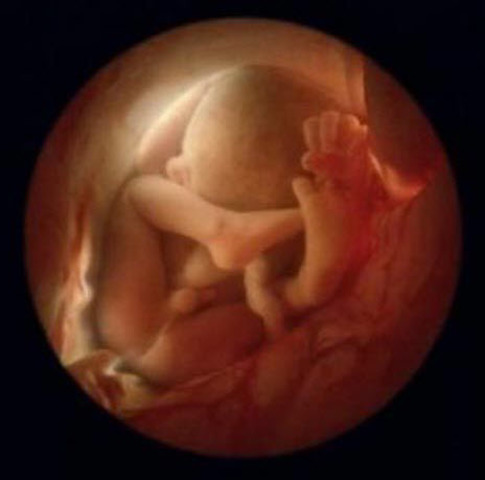

La posición habitual es semiflexionada con las manos a la altura de la barbilla y los pies cruzados por debajo de la salida del cordón umbilical.

Tu hijo flota en el agua, ya que todavía el saco amniótico es muy espacioso. Esto permite al bebé moverse de un lado a otro, darse la vuelta, girarse, dar patadas y cambiarse de posición varias veces en un día.